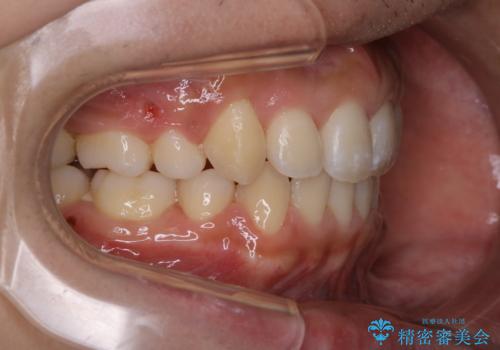

- オーディションで歯並びを指摘されたことから一念発起して矯正治療を行う事にした方です。

親知らずと、前から4番目の歯を抜歯してワイヤー装置による矯正治療を行いました。

人前に出ることが多いため、当初は目立たない装置をご希望されていましたが、歯の移動距離が大きいため効率よく歯を動かせる表側の装置での治療をお勧めしました。すれ違ってしまっていた奥歯もしっかり治すことができました。